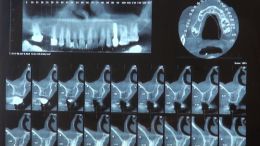

گالری » دوره های آموزشی » دوره بازسازی استخوان GBR - تاریخ برگزاری 10 و 11 مردادماه 98 » اصول مبانی GBR - مدرس دکتر عمید

اصول مبانی GBR - مدرس دکتر عمید

اصول مبانی GBR

- جراحي توسط دکتر عميد از اساتید گروه علمی بن تاژ